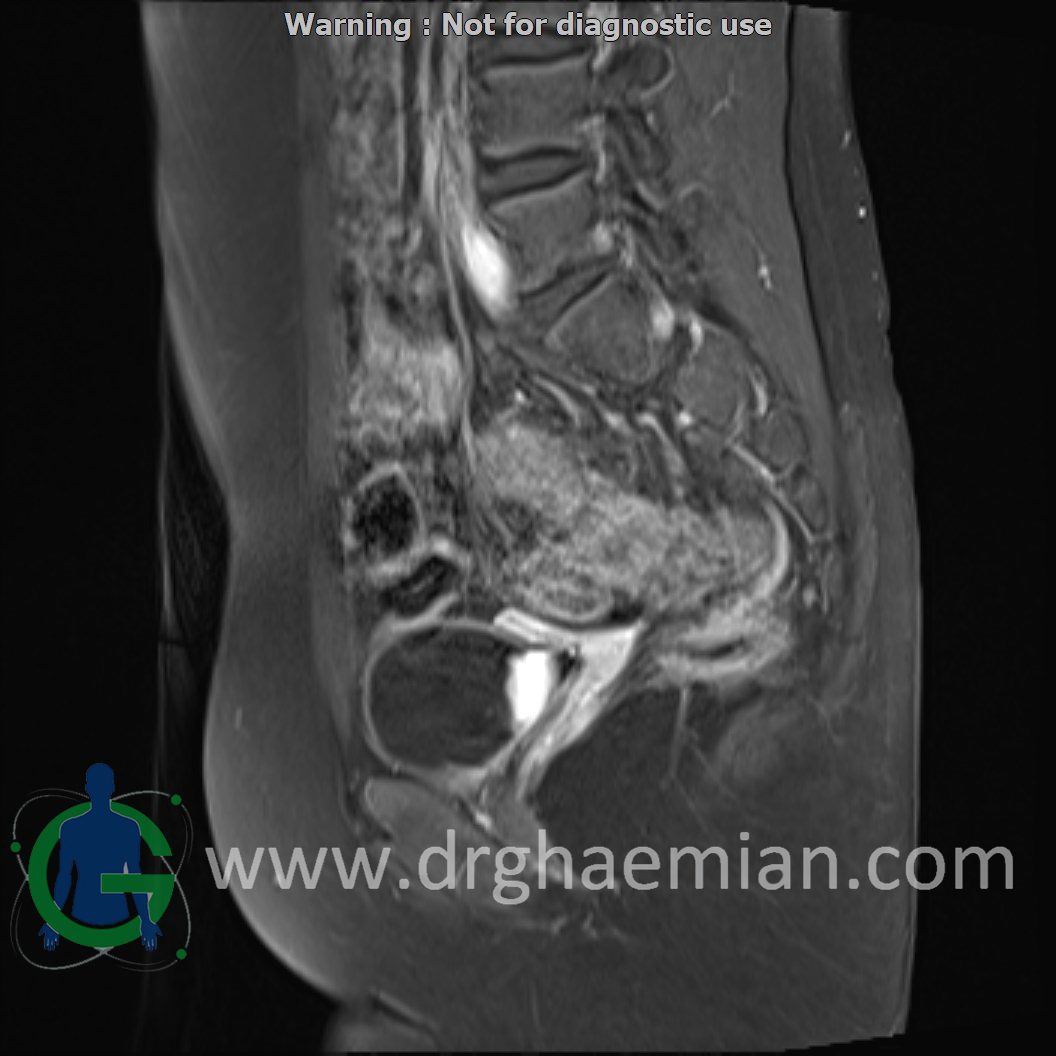

ام آر آی لگن یک روش تصویربرداری است که از طریق دستگاهی با آهنرباهای قوی و امواج رادیویی از ناحیه بین استخوان های ران تصاویری می سازد.در این کیس دیسژنزی غدد جنسی همراه با رحم و واژن هیپوپلاستیک نشان دهننده سندرم سویر ….

Complete gonadal dysgenesis with hypoplastic uterus & vagina suggestive of swyer syndrome is seen.

Clinical crrelation is recommended.